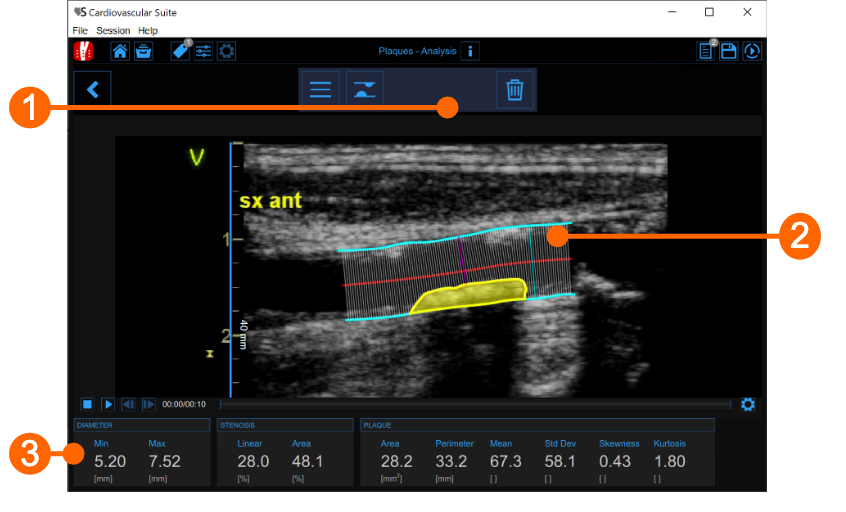

The plaque analysis window contains the following components:

- Setup panel

It contains the controls for tracing of the vessel borders, drawing a plaque and delete it.

- Plaque analysis tool

The Trace borders  button is used to manually trace the borders of the vessel. The user has to trace point-by-point the vessel edges and the software interpolates them. It is possible to modify the points by dragging them, as shown in the following picture.

button is used to manually trace the borders of the vessel. The user has to trace point-by-point the vessel edges and the software interpolates them. It is possible to modify the points by dragging them, as shown in the following picture.

After the two borders are traced, the software automatically compute the minimum and maximum values of the diameter and the linear and circular values of the stenosis. The Draw plaque  button is used to manually draw the profile of a plaque. The user has to trace point-by-point the plaque profile and the software interpolates them. Also in this case, it is possible to modify the points by dragging them and to delete a plaque, as shown in the following picture.

button is used to manually draw the profile of a plaque. The user has to trace point-by-point the plaque profile and the software interpolates them. Also in this case, it is possible to modify the points by dragging them and to delete a plaque, as shown in the following picture.

After the plaque is drawn, the software automatically computes its area, perimeter, and the mean, standard deviation, skewness, and kurtosis of its grey level.

- Data panel

This panel contains the computed values. In particular, it shows the minimum and maximum values of the diameter and the linear and circular values of the stenosis. In addition, if a plaque has been drawn, it also displays its area and perimeter, and the mean, standard deviation, skewness, and kurtosis value of its grey level.